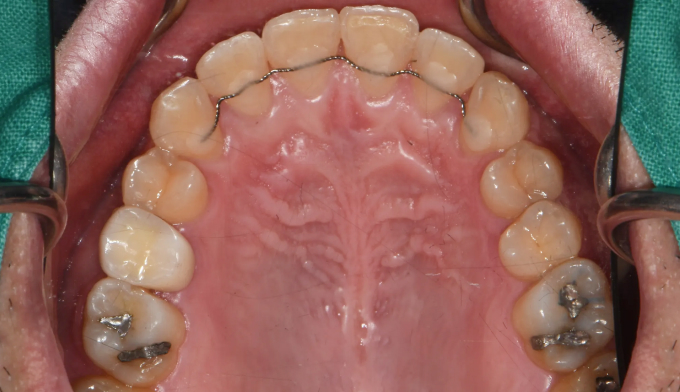

턱근육의 과활성은 교정치료를 어렵게 만드는 요인 중 하나입니다. 최대한 미소선에 맞추어 앞니를 배열하고 과개교합도 개선하였습니다. 턱근육의 이완을 돕고자 보톡스 치료도 동반하였습니다.

위 앞니 잇몸선의 비대칭도 관찰되어 잇몸절제술도 권유드렸으나 현재 상태에 만족하셔서 교정치료를 8개월만에 종료하였습니다.